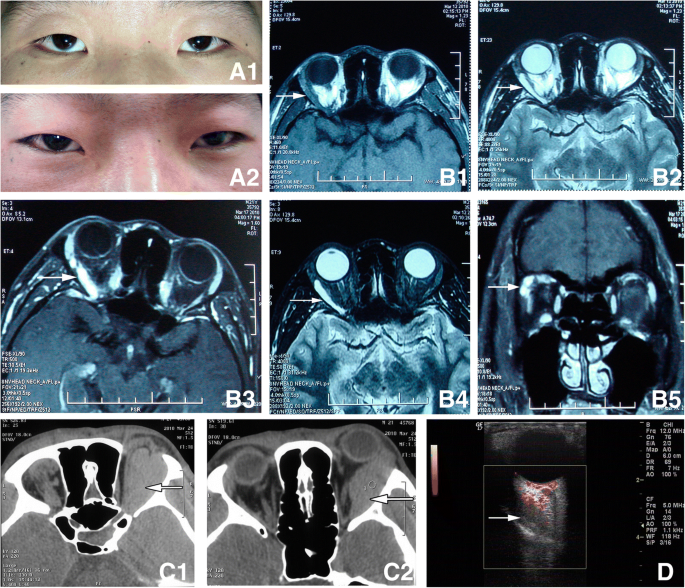

None of the cases had infection, complication of the cavernous sinus embolization, or necrosis of the local soft tissue (including application in the sub-conjunctiva lesions). In total, 15 cases had no complications. 9 cases had early post-surgical complications including mild ocular movement disorder. Follow-up of these cases showed that they all recovered gradually within three months. 2 cases had ptosis and recovered 1–2 months after the surgery. 2 cases had eyelid deformity and underwent plastic surgery one year later for cosmetic improvement. In addition, 2 cases had numbing of the skin, and 1 case had invagination of the eyeball. It is worth mentioning that one patient with intra-orbital varicosity had intermittent exophthalmos before surgery. Pre-operation imaging indicated that the malformed blood vessel was located in extraconal orbital compartment. When the malformed vessel dilated, it pushed the optic nerve displacement. During the surgery medical glue was applied and the lesion was resected. Because the lesion was large and deep into the orbital apex, a few glue residues at the orbit apex were not removed. Then a small tungsten wire wrapped by gelatin sponge was used as packing hemostasis. The size of the pupils was normal in post-operation. Pressure bandaging was applied as usual. The 3rd day after surgery vision monitoring showed uncertain light perception. Central retinal artery occlusion (CRAO) was confirmed after a promptly detailed ocular examination. Treatment for CRAO included ocular massage, administration of oxygen, sublingual nitroglycerin, and decreasing the intraocular pressure with intravenous mannitol. Patient condition improved with effective immediate rescue. Patient vision was 20/16 pre-operation, and 20/32 at the time of discharged (Fig. 2).

Patient with intra-orbital varicosity A1. Appearance when the patient was sitting, Hertel’s exophthalmometry revealed 2 mm of enophthalmos of right eye; A2. Appearance when the patient had bent down and bowed his head for 1 min, 4 mm of proptosis of right eye than the left; B. Horizontal MRI and coronal scan(supine position), showed a superotemporal ribbonlike mass in the extra-conal orbital compartment. The lesion displayed isointense on T1-weighted images (B1), hyperintense on T2-weighted images (B2), and significantly heterogenous contrast enhancement on enhanced and fat suppression MRI scan (B3–5). C. Axial CT scanning (prone position, the symbol of the right eye “R” was opposite to that on the MRI) showed a right superotemporal huge spindle-shaped homogenous mass pushing the eyeball to protrude and extending to the orbital apex. The superior rectus, lateral rectus and optic nerve were difficult to identify. D. CDFI (30 mmHg pressure was applied to the neck by the cuff of sphygmomanometer) showed a ribbonlike well defined hypoechoic mass expanded. The lesion was affecting the lateral rectus and pushed the optic nerve moving inward. There were signals of blood flow in the lesion. The arrow pointed to the lesion in Fig. 2